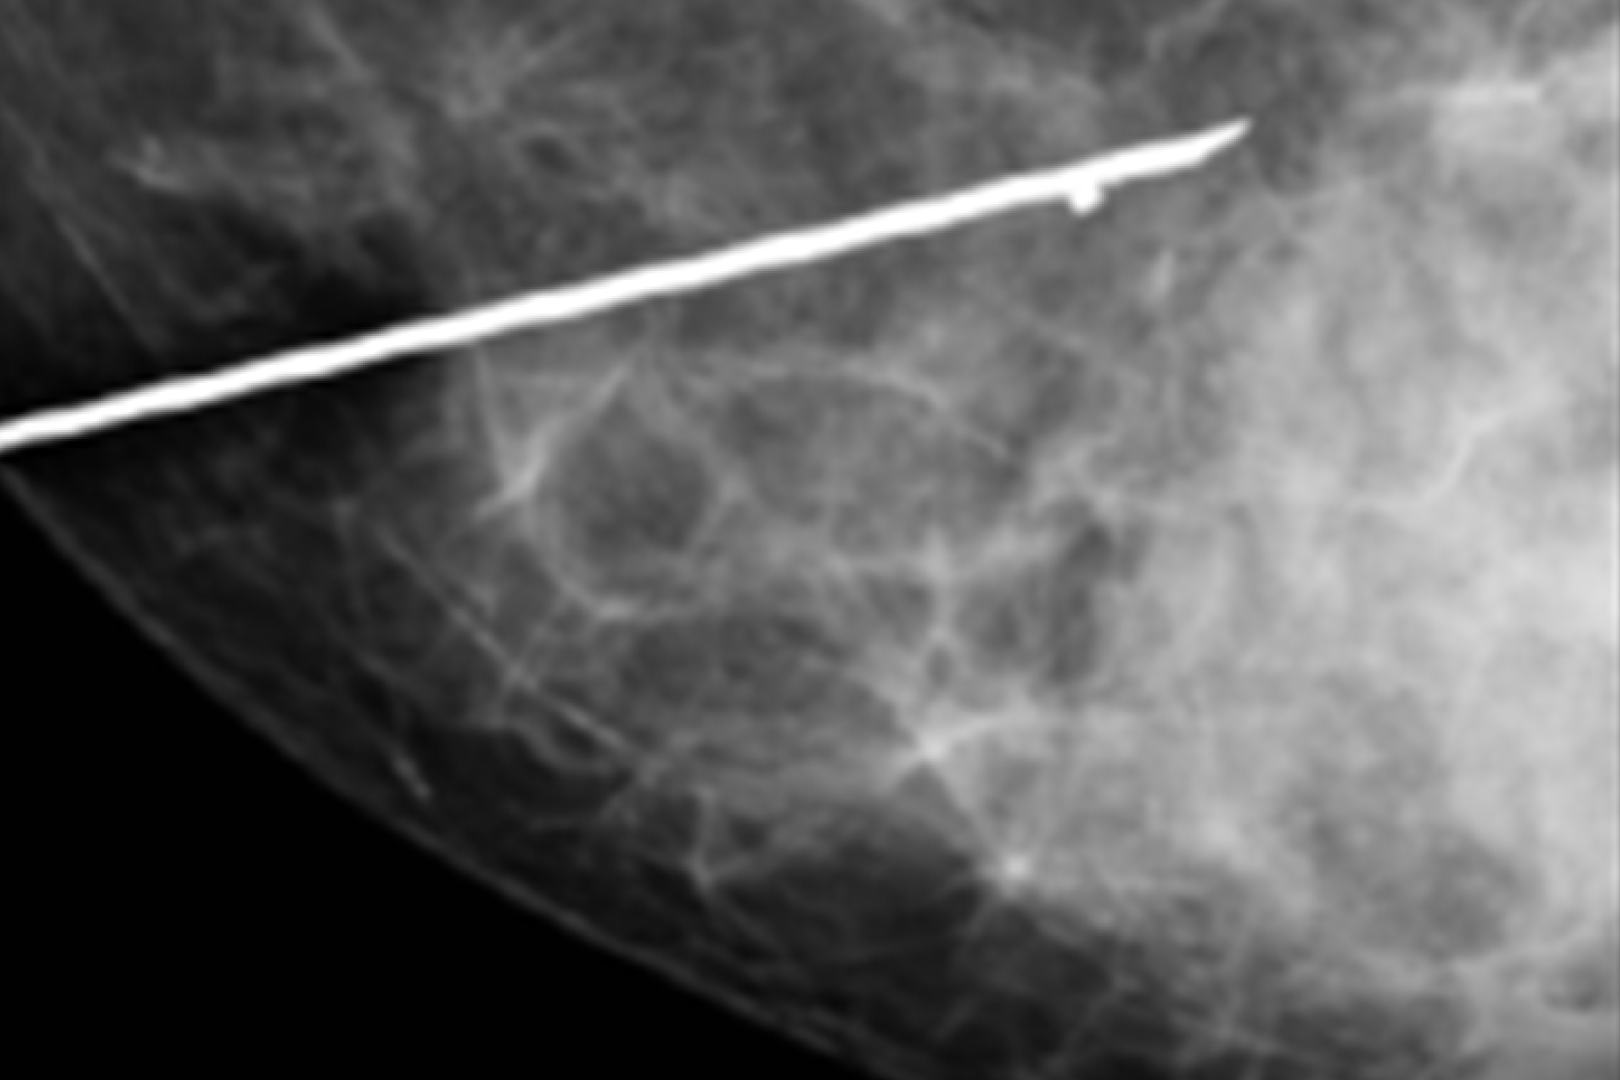

HD Live quinta dimensión, Imágenes de volumen con profundidad y claridad, que aportan un realismo anatómico para un mejor diagnóstico.